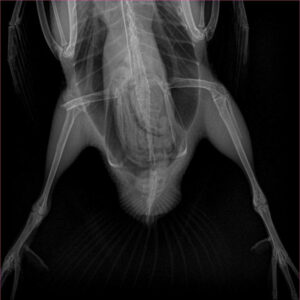

X-ray showing broken femur of hooded merganser“When he did move he was struggling with walking,” wrote Robert in an account posted on his Facebook. Robert examined him, looking for any sign of injury but found none. When the merganser (named “Howard” by Robert) did finally attempt to take off, the bird couldn’t achieve much height and ended up flying into a parked car. The bird definitely needed medical attention, so Robert rode the bird home on his bike and contacted Carolina Waterfowl Rescue.

Once at our rehabilitation center, we examined this juvie and observed what felt like trauma in the bird’s right leg. Howard weighed 440 grams at intake (about 15.5 ounces). To get a better sense of the bird’s injury, we took radiographs and saw a clear distal fracture of the right femur, an injury that was unlikely to heal on its own. But, with some expert guidance from our trained rehabbers and staff veterinarian, we are still hopeful to return this beautiful merganser to the wild!